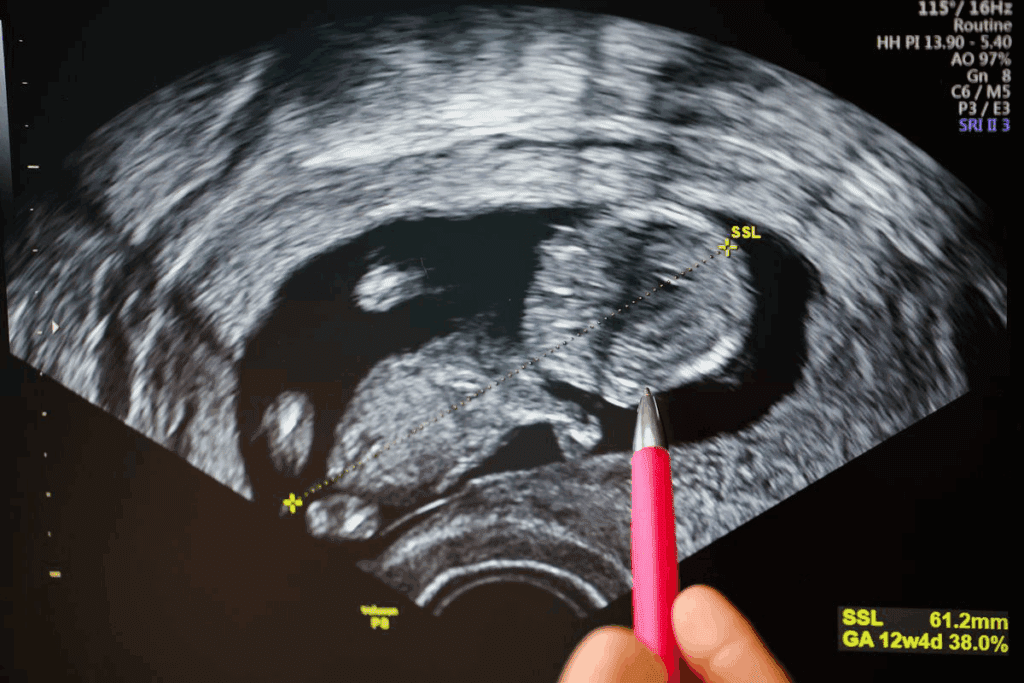

During the fifth week, the embryo’s major milestones include the formation of the neural tube. This will eventually develop into the brain and spinal cord. The heart begins to divide into chambers, and the foundations for the respiratory and digestive systems are established. The embryo is about 2-3 millimeters in length and is surrounded by a gestational sac, which is visible on an ultrasound.

By 5 weeks gestation, a transvaginal ultrasound can typically reveal a gestational sac. The embryo itself might be too small to detect. As the embryo grows, it will become more visible on subsequent ultrasounds.

Effectiveness of Transvaginal Ultrasound at 5 Weeks

Transvaginal ultrasound is more effective at 5 weeks. It gives a closer look at the embryo. This method can show a gestational sac at 5 weeks, confirming pregnancy early. The probe’s close position to the uterus means clearer images, which is key in early pregnancy.

“Transvaginal ultrasound is vital in early pregnancy,” it helps spot pregnancy-related structures early. This is critical for women with a history of ectopic pregnancies or other issues.

What Can Be Seen on a 5-Week Ultrasound

Gestational Sac Visualization

By 5 weeks, a gestational sac might show up on a transvaginal ultrasound. This sac is a key early sign of pregnancy. It looks like a small, fluid-filled area around the embryo.

By 5–6 weeks, you might see a fetal pole (the early embryo) and maybe even a heartbeat. The fetal pole is the embryo itself. Seeing a heartbeat is a good sign that the pregnancy is healthy.

Seeing cardiac activity is a key sign of the embryo’s health and if it’s viable.

The 6-7 Week Window

Doctors usually suggest the 6-7 week mark for the first ultrasound. At this time, the embryo’s growth can be checked well, and any problems can be spotted early. Waiting until 6 to 7 weeks helps get clearer results about the pregnancy’s health.